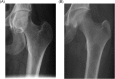

Gaucher disease (GD) is a rare, genetic lysosomal disorder leading to lipid accumulation and dysfunction in multiple organs. Involvement of the skeleton is one of the most prevalent aspects of GD and a major cause of pain, disability, and reduced quality of life. Uniform recommendations for contemporary evaluation and management are needed. To develop practical clinical recommendations, an international group of experienced physicians conducted a comprehensive review of 20 years' of the literature, defining terms according to pathophysiological understanding and pointing out best practice and unmet needs related to the skeletal features of this disorder. Abnormalities of bone modeling, reduced bone density, bone infarction, and plasma cell dyscrasias accompany the displacement of healthy adipocytes in adult marrow. Exposure to excess bioactive glycosphingolipids appears to affect hematopoiesis and the balance of osteoblast and osteoclast numbers and activity. Imbalance between bone formation and breakdown induces disordered trabecular and cortical bone modeling, cortical bone thinning, fragility fractures, and osteolytic lesions. Regular assessment of bone mineral density, marrow infiltration, the axial skeleton and searching for potential malignancy are recommended. MRI is valuable for monitoring skeletal involvement: It provides semiquantitative assessment of marrow infiltration and the degree of bone infarction. When MRI is not available, monitoring of painful acute bone crises and osteonecrosis by plain X-ray has limited value. In adult patients, we recommend DXA of the lumbar spine and left and right hips, with careful protocols designed to exclude focal disease; serial follow-up should be done using the same standardized instrument. Skeletal health may be improved by common measures, including adequate calcium and vitamin D and management of pain and orthopedic complications. Prompt initiation of specific therapy for GD is crucial to optimizing outcomes and preventing irreversible skeletal complications. Investing in safe, clinically useful, and better predictive methods for determining bone integrity and fracture risk remains a need. © 2019 The Authors. Journal of Bone and Mineral Research Published by Wiley Periodicals Inc.